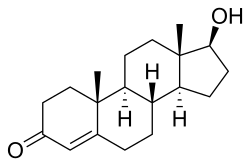

During puberty in males, hypertrophy occurs at an increased rate. Natural hypertrophy normally stops at full growth in the late teens. As testosterone is one of the body's major growth hormones, on average, males find hypertrophy much easier (on an absolute scale) to achieve than females, and, on average, have about 60% more muscle mass than women.[12] Taking additional testosterone, as in anabolic steroids, will increase results. It is also considered a performance-enhancing drug, the use of which can cause competitors to be suspended or banned from competitions. Testosterone is also a medically regulated substance in most[13][14] countries, making it illegal to possess without a medical prescription. Anabolic steroid use can cause testicular atrophy, cardiac arrest,[15] and gynecomastia.[16]